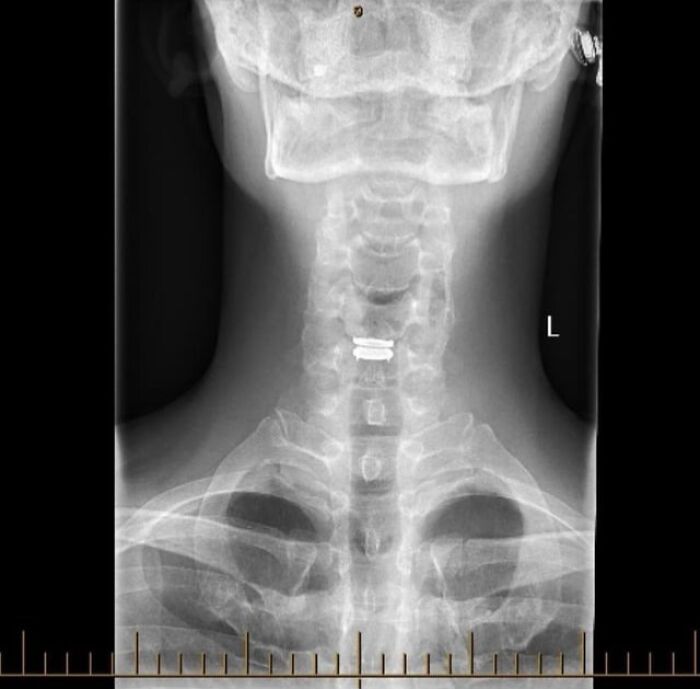

#20 Thought You Good People Might Like To See My New C5/C6 Disc

Image source: medical